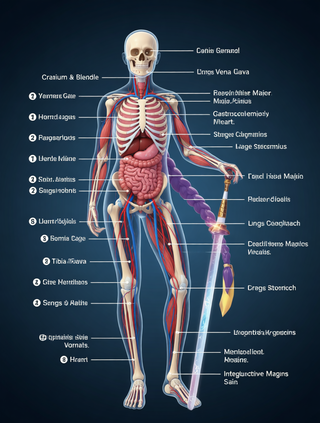

Creates ultra-detailed, multi-layer 3D anatomical visualizations from reference photos.Open

Creates ultra-detailed, multi-layer 3D anatomical visualizations from reference photos.Open

Transform photos into scientific anatomical illustrations.Open

Transform photos into scientific anatomical illustrations.Open